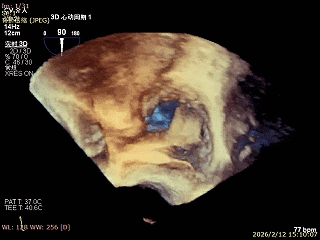

患者全麻下行TEER手术。穿刺患者右侧股静脉,在X线及食道超声指导下完成房间隔穿刺成功获得足够穿刺高度。再将加硬导丝送至左上肺静脉,20F股静脉扩张鞘充分扩张股静脉穿刺部位,沿加硬导丝将可操纵导引导管(SGC)送入左房。沿SGC送入XTR夹子完成骑跨,使用M旋钮使夹子指向二尖瓣。调整MitraClip输送系统顺利到达二尖瓣目标位置,TEE指导下左房内完成弹道测试和Orientation调整。缓慢将XTR夹子送入左室,并三维再次确认夹子轴向和反流位置,缓慢上提夹子使夹臂成功捕获瓣叶,Gripper Down夹持前后瓣叶并缓慢关闭夹臂,夹持后反流降至微量。评估后将夹子释放,释放后反流微量夹子稳定。术后复查超声证实夹合组织充分,显示微量残余分流。肺静脉多普勒波形恢复正常。手术时间持续约1.5小时。

三维观察血流,调整Orientation

TEE引导夹子送入左室捞捕瓣叶

复核Orientation

Gripper Down夹持前后瓣叶并关闭夹臂

夹持后反流降至微量

组织桥稳定